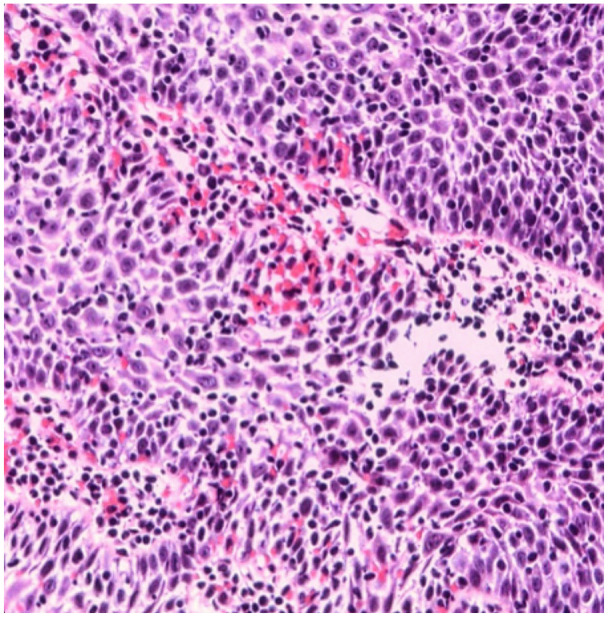

Lymphocytic esophagitis (LE) is an uncommon subtype of esophagitis defined by persistent esophageal inflammation characterized by a high count of intraepithelial lymphocytes with scarce granulocytes. Although LE can present with atypical features such as chest pain, its clinical presentation can mimic that of gastroesophageal reflux disease or eosinophilic esophagitis, highlighting the importance of biopsy in diagnosing LE. Studies are still limited in understanding the pathophysiology behind this disease warranting further research. A 47-year-old female patient sought medical care with a chief complaint of recurrent substernal chest pain for the past year. An esophagogastroduodenoscopy was performed and showed patchy linear esophageal erosions and mucosal edema in the middle third of the esophagus with mild erythema. Biopsies revealed intraepithelial lymphocytosis with more than 40 lymphocytes per high-power field, corroborating a diagnosis of LE. Patient reported improvement after receiving high dose of proton pump inhibitor (PPI) on her first follow-up, advised to follow a low-acid diet and an annual endoscopy to monitor her response to treatment. Lymphocytic esophagitis often presents with symptoms that overlap with other esophageal diseases explaining the possible errors in underdiagnosing it as reason behind non-cardiac chest pain. This case plays an instrumental role in changing the way physicians translate unexplained chest pain, adding LE to their list of differential diagnosis as prompt detection slows us to start management with PPIs quicker and lessen the burden of symptoms on the patient. Standardized treatment approaches and further studies are required to clarify the connection between LE and non-cardiac chest discomfort.